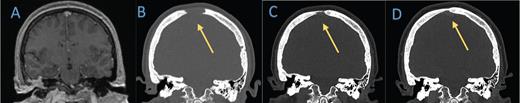

Coronal computed tomography (CT) head bone window demonstrates lytic lesion along the frontal cranium near the vertex which is not evident on the A) brain MRI from 2019. B-D) Subsequent head CTs obtained nine months later show significant interval decrease in size of the lytic lesions. Follow-up head CT in eight months demonstrates further evidence of healing.